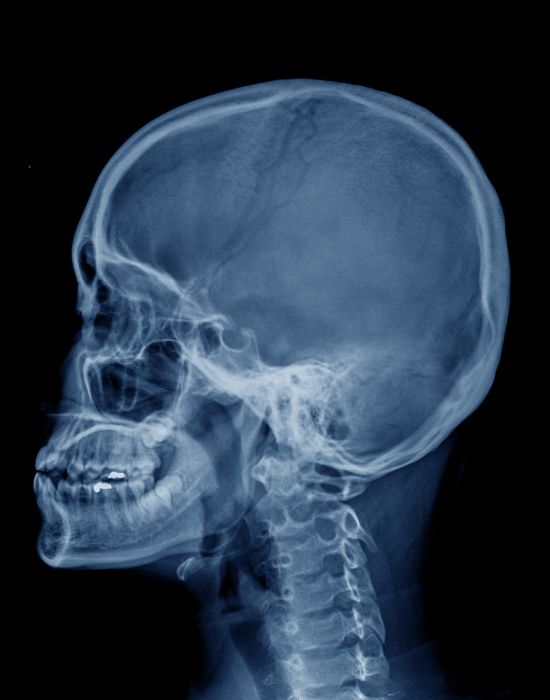

Радіологічна діагностика скроневої кістки

Радіологічна діагностика скроневої кістки: Ключові аспекти для роботи рентгенолаборанта